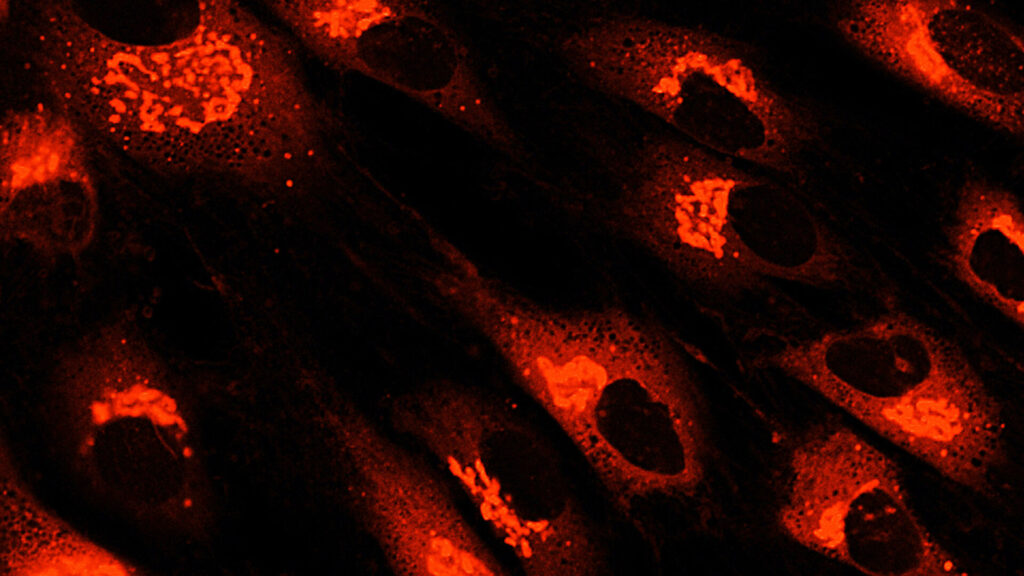

如今,MSC一詞描述了一類細(xì)胞,歷史上被稱為間充質(zhì)干細(xì)胞、間充質(zhì)基質(zhì)細(xì)胞和醫(yī)學(xué)信號(hào)細(xì)胞等。間充質(zhì)干細(xì)胞的臨床用途主要?dú)w因于它們的關(guān)鍵生物學(xué)特性,其中包括:

根據(jù)臨床前和臨床證據(jù),間充質(zhì)干細(xì)胞治療免疫和炎癥性疾病顯示出特別的前景,研究人員正在探索間充質(zhì)干細(xì)胞衍生療法和外泌體在治療自身免疫性疾病、骨關(guān)節(jié)炎、炎癥性肝病、肺部疾病、移植排斥等方面的臨床應(yīng)用。人們對(duì)同種異體間充質(zhì)干細(xì)胞的興趣也日益濃厚,因?yàn)樗梢宰鳛楝F(xiàn)成產(chǎn)品提供。

如今,間充質(zhì)干細(xì)胞正在新興應(yīng)用中得到應(yīng)用,例如組織工程、類器官、外泌體生產(chǎn)、藥妝品和培養(yǎng)肉。此外,人們正在探索iPSC衍生的MSC在MSC療法開發(fā)中的作用,因?yàn)檫@些MSC可以經(jīng)濟(jì)地以幾乎無(wú)限的規(guī)模批量生產(chǎn)。